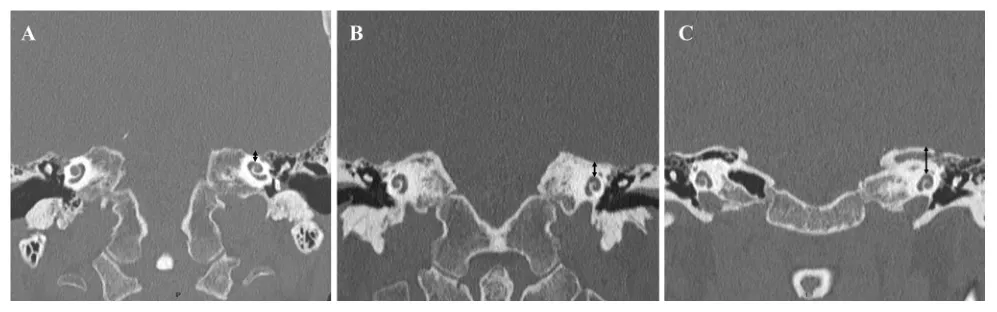

冠状位CT扫描还需重点关注耳蜗第一转与周围皮质骨及中颅窝底之间的间距。当该距离仅为2-3毫米时,菱形窝的可磨除空间严重缩窄,强行推进将大幅增加损伤耳睫和膝状神经节的风险;而当距离达到4-8毫米时,无需过度逼近耳蜗即可获得足够的后颅窝视野,安全性显著提升。

图8. 中颅窝底与耳蜗深度之间的关系。CT显示耳蜗到中颅窝底表面距离的变化。三个不同的病例的距离分别为2.1毫米(A)、4.8毫米(B)和8毫米(C)。